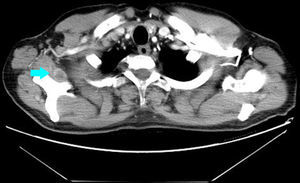

Varón de 56 años, fumador de 40 paquetes/año, que acude a la consulta por presentar dolor a nivel del musculo trapecio derecho, después de un partido de tenis. Entre sus antecedentes personales destaca un infarto de miocardio inferior 15 años antes, a tratamiento con simvastatina 10mg, AAS 100mg y atenolol 50mg. A la exploración se palpaba una discreta tumefacción dolorosa en el músculo trapecio. El cuadro es interpretado inicialmente como una contractura muscular tratándolo con AINE, relajantes musculares y fisioterapia. Un mes más tarde acude nuevamente a la consulta por astenia y empeoramiento del dolor que se había extendido a la musculatura pelviana y antebrazo derecho. No refería cefalea, tos, disnea ni fiebre. En la analítica destaca una VSG de 70 y PCR 4. Se realiza una radiografía de tórax donde se aprecia una masa parahiliar derecha. El TAC torácico y abdominal evidencio una masa hiliar derecha de 5,5cm y múltiples metástasis musculares, al menos en el subescapular derecho (fig. 1), psoas izquierdo, recto anterior izquierdo y musculatura glútea (fig. 2).